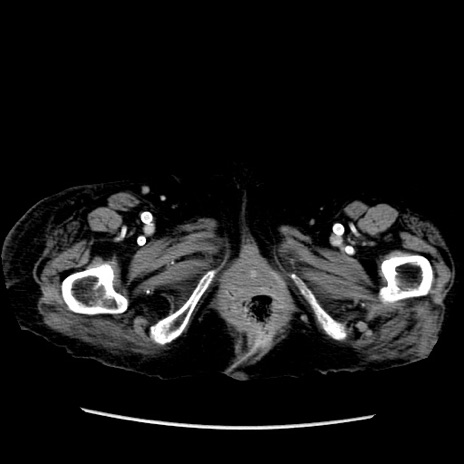

症例14(横断像)

【症例】 90歳代女性

【主訴】 腹痛・嘔吐

【現病歴】今朝から左側腹部痛を認めた。 経過観察していたが、嘔吐を認めたため来院。

【既往歴】 子宮癌術後

【身体所見】 意識清明、BP 127/54mmHg、P 98bpm Sp02 95%(RA)、BT 35.8°C、腹部平坦・軟腸ぜん動音聴取良好、右下腹部圧痛(+) 反跳痛なし

【データ】WBC 9800、CRP 0.46